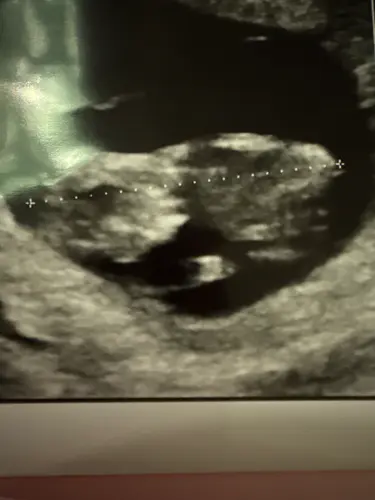

Wat zal het worden meisje of jongetje鈽猴笍

Ik denk een jongen

Waar kijk je precies naar? Ik dacht dat de nub dan altijd naar boven moest steken, ik snap het niet meer haha. Toch maar wachten tot de geslachtsecho

Ik blij echt bij een meisje 馃槈

Ja ik dacht dus zelf echt dit ook (hoop het stiekem wel!) maar snap niet dat mensen jongen zeggen daardoor want die zie ik er niet in馃き馃ぃ